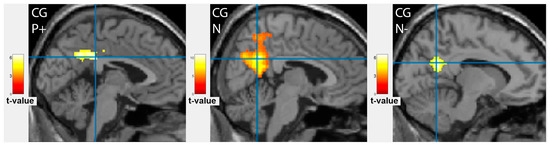

3.1. Brain Activation Patterns in Depressive Patients before Treatment (Background)

| Cluster Location | Emotion | Extent | t-Value | p (FWE Corrected) | MNI Coordinates |

|---|---|---|---|---|---|

| Patients group before therapy | |||||

| Frontal cortex | |||||

| Left middle frontal gyrus, BA46 | N | 1457 | 6.24 | <0.001 | −48;38;20 |

| Right inferior frontal gyrus, BA46 | N | 632 | 8.83 | 0.001 | 50;40;4 |

| Right middle frontal gyrus | N- | 2064 | 10.89 | <0.001 | 54;20;30 |

| Right inferior frontal gyrus | P+ | 2368 | 8.91 | <0.001 | 46;22;8 |

| Occipital cortex | |||||

| Left fusiform gyrus, BA37 | N | 2001 | 10.59 | <0.001 | −40;−70;−18 |

| Right inferior occipital gyrus | N- | 3095 | 16.45 | <0.001 | 40;−70;−16 |

| Right occipital cortex, BA17 | P+ | 4282 | 13.27 | <0.001 | 18;−96;−4 |

| Left middle occipital gyrus, Cuneus | P+ | 2017 | 10.8 | <0.001 | −24;−92;6 |